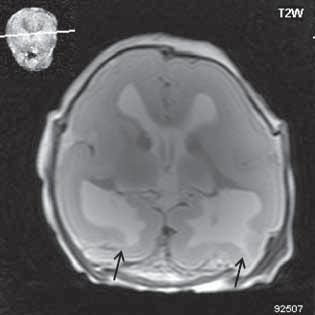

Obr. I.1.8a Dandy-Walkerova malformace, rozšířená IV komora (tvar klíčové dírky)

Obr. I.1.8b Dandy-Walkerova malformace, rozšířená IV komora široce komunikující s cisterna magna, hypotrofie mozečku (snímky zapůjčeny z archivu prim doc MUDr M Mechla, Ph D, MBA)

Obr. I.1.8c Dandy-Walkerova malformace, rozšířená IV komora široce komunikující s cisterna magna, hypotrofie mozečku (snímky zapůjčeny z archivu prim doc MUDr M Mechla, Ph D, MBA); stejný pacient jako na obr I 1 8b

Obr. I.1.8d Dandy-Walkerova malformace, rozšířená IV komora široce komunikující s cisterna magna, hypotrofie mozečku, vysoký úpon tentoria (šipka) (snímky zapůjčeny z archivu prim doc MUDr M Mechla, Ph D, MBA); stejný pacient jako na obr I 1 8b, c

D-W malformace je charakterizována hypoplazií vermis mozečku, rozšířením IV. mozkové komory, která se často cysticky vyklenuje dorzálně a může imitovat arachnoidální cystu, rozšířením zadní jámy lební a vysokým úponem tentoria s confluens sinum nad lambdovým švem. Okcipitální kost může být vlivem tlakových změn remodelována, existují i případy s porušením její kontinuity a encefalokélou. Hydrocefalus pozorujeme v 80 %, častá je přítomnost dysgeneze corpus callosum, schizencefalie.

D-W variant byl vyčleněn pro případy, kdy všechny základní příznaky nemusí být plně vyjádřeny nebo může některý zcela chybět. Bývá přítomna hypoplazie mozečku, což je dominantní příznak, IV. komora je obvykle rozšířena, někdy pozorujeme, že tvarem připomíná na axiální řezu „klíčovou dírku“, zadní jáma lební naopak rozšířena nebývá.